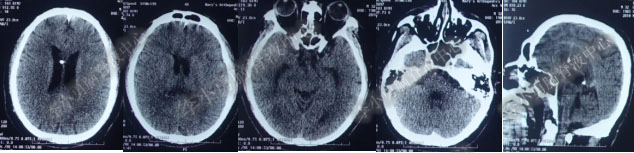

【患者在李小勇脑脊液中心治疗过程和结果】

2016年5月9日因“间断性眩晕半月,恶心呕吐一周”以“梗阻性”脑积水,第1次住入北京某企业三级医院神经外科内镜组。2016年5月10日(入院后第2天)行头部MRI(图-1)检查示脑室系统扩张。

图-1:2016年5月10日头部MR

术后7天(2016年5月18日),症状有所缓解,复查头部MRI(图-2)幕上脑室较术前缩小,但是“四脑室仍扩张”,医生认为 “正常”于术后8天(2016年5月19日)出院。

图-2:2016年5月18日头部MRI

图-3:2016年9月26日头部MRI

第1次内镜术后330余天即11个月(2017年4月),又开始出现头晕症状并逐渐加重。2017年6月13日(第1次内镜术后367天),行头部MRI(图-4)检查显示全脑室系统扩大。

图-4:2017年6月13日头部MRI